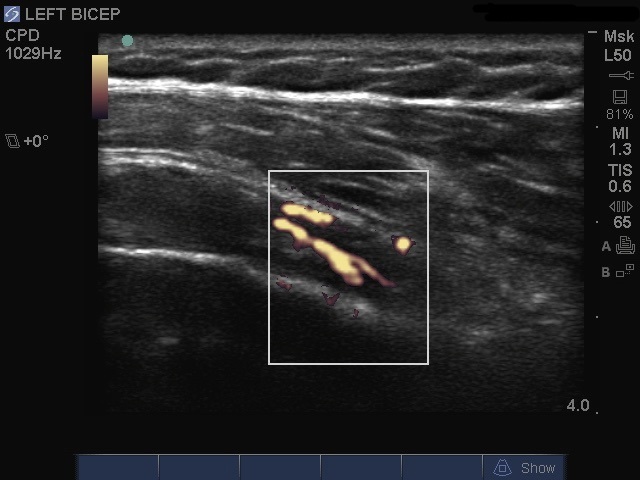

Image - Épaule : Ténosynovite du biceps, coupe grand axe en Doppler puissance